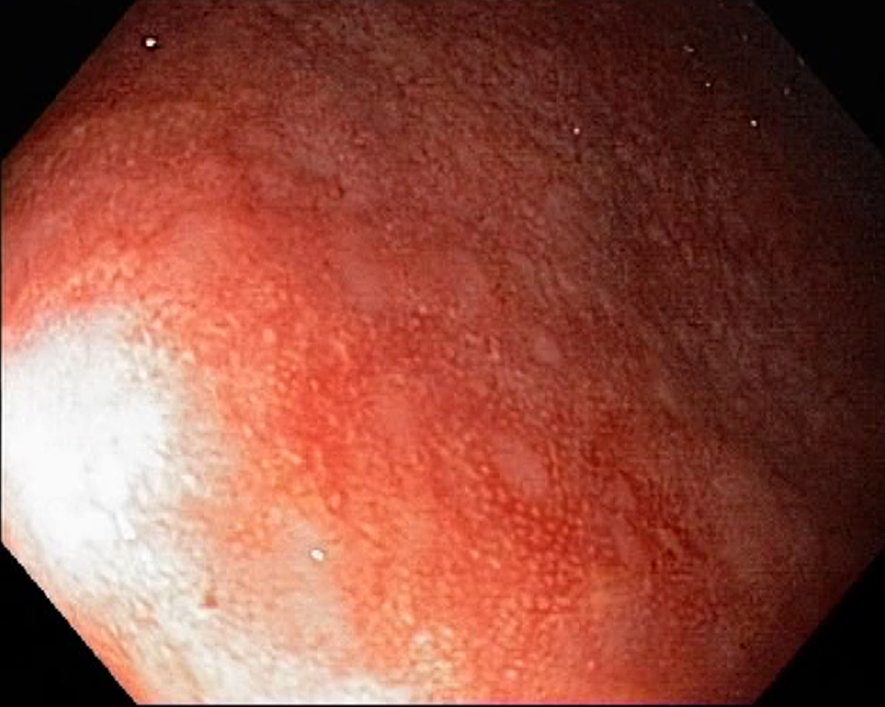

Campylobacter-Colitis